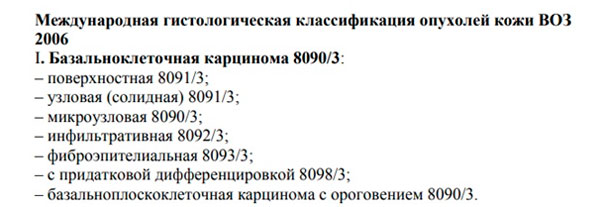

Код мкб 10 атерома головы

Код мкб 10 атерома головы 109 фото